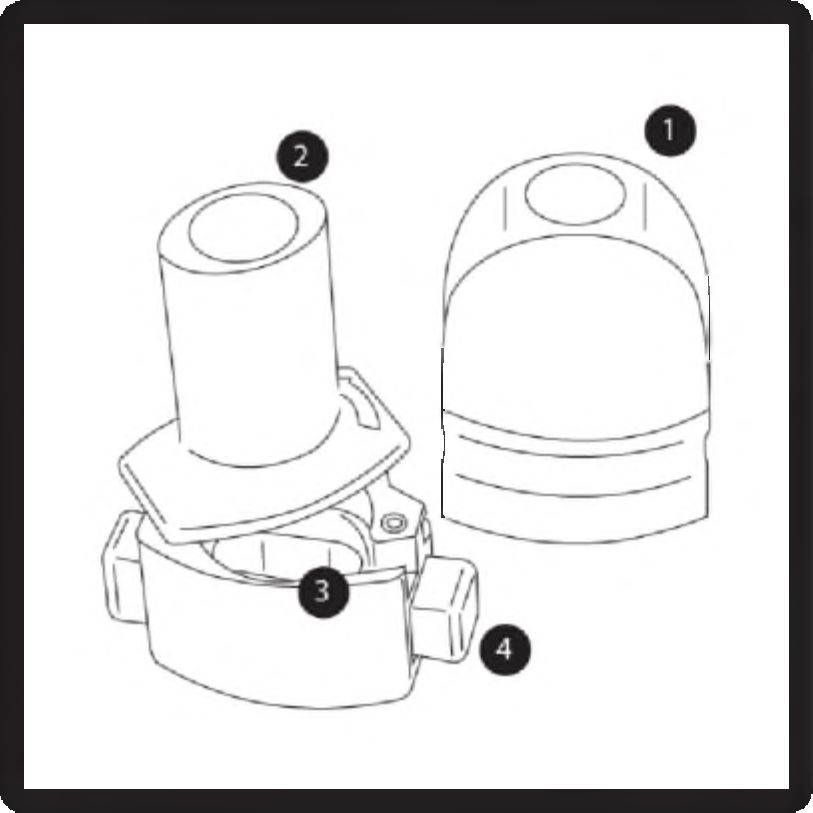

1. Kapak

2. Ağızlık parçası

3. Kapsül haznesi

4. Delme düğmesi